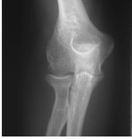

Figure 62-1 Inflammatory arthritis disease progression.

Figure 62-2 A: Stage I rheumatoid arthritis. B: Stage I rheumatoid arthritis.